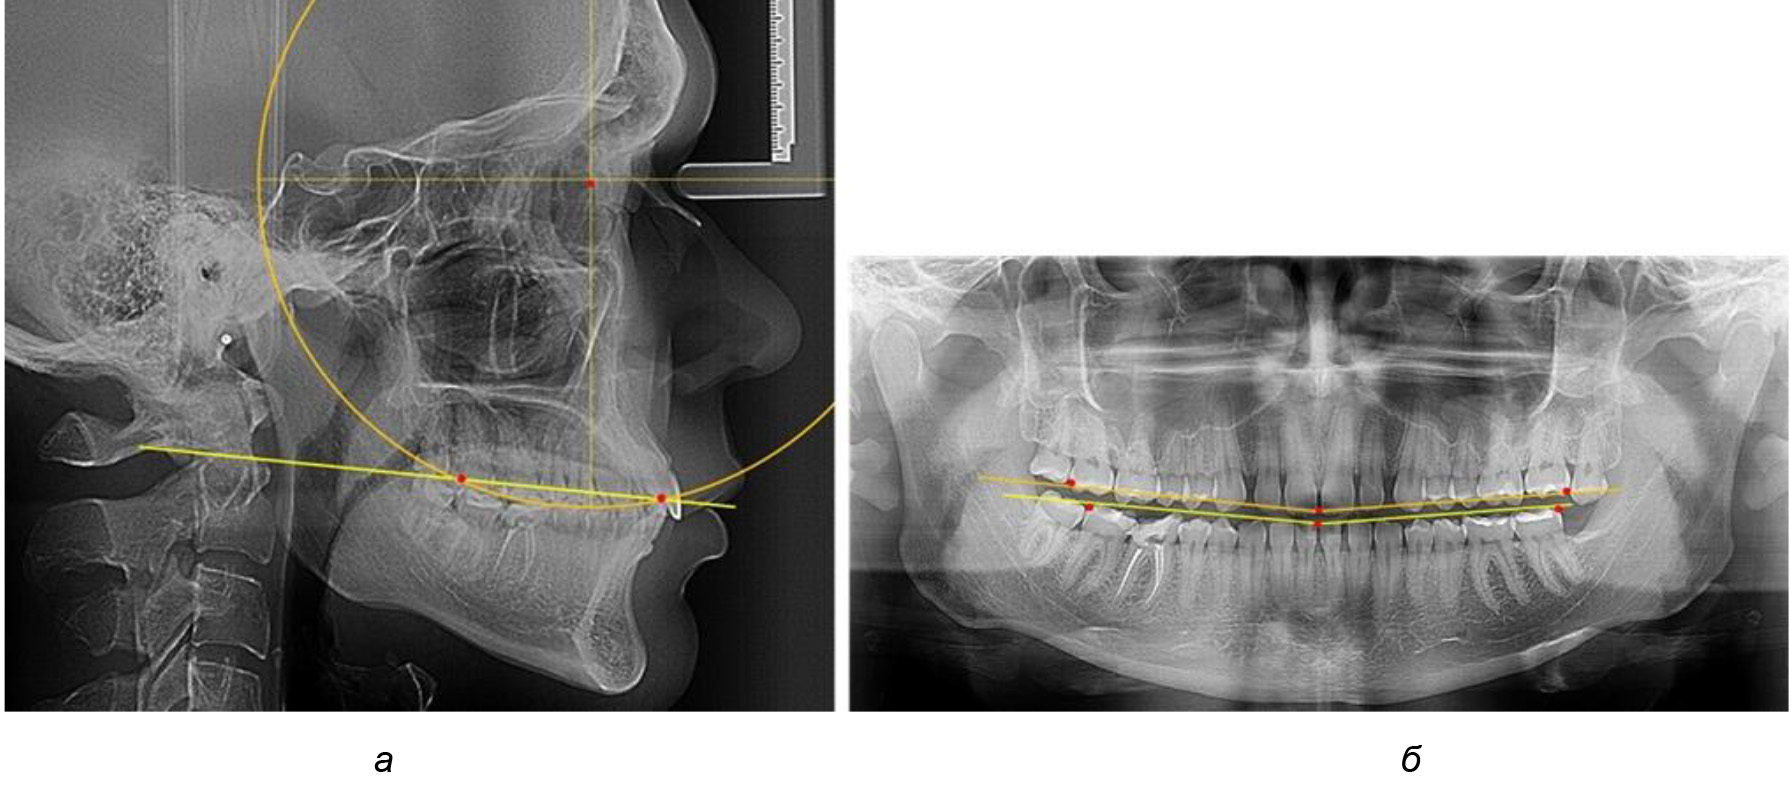

У людей с аномалиями окклюзии по сагиттали в 1-й подгруппе обследовано 9 человек. Обращает на себя внимание увеличение глубины кривой Spee, что нами расценивалось, как патологическая форма кривой линии окклюзии.

Глубина кривой Spee в среднем по 2-й подгруппе составила (5,69 ± 1,57) мм, что было достоверно больше, чем у людей с физиологической окклюзией (р ˂ 0,05). Достоверных различий с показателями, полученными при анализе ТРГ и ОПТГ, нами не отмечено (р ˃ 0,05). Отношение радиуса окружности к сагиттальному размеру окклюзионной линии в среднем по подгруппе составляло 1,372 ± 0,042 и не соответствовало числу Фибоначчи, что может быть использовано в качестве диагностического критерия определения патологической формы кривой Spee. После лечения пациентов техникой «прямой» дуги было отмечено незначительное увеличение сагиттального размера окклюзионной лини в среднем на (2,12 ± 0,77) мм. Однако окклюзионная линия практически касалась окклюзионного контура всех жевательных зубов, и отмечалось практически полное отсутствие кривой Spee.

Таким образом, проведенное лечение техникой «прямой» дуги способствует нормализации окклюзионного равновесия и торку передних зубов, однако не соответствует оптимальному окклюзионному статусу, характеризующему физиологическую окклюзию. При этом величина нижнечелюстного угла оставалась на прежнем уровне (рис. 5).

Рис. 5. Особенности ТРГ при патологической кривой Spee до лечения (а) и после лечения (б) техникой «прямой» дуги

Во 2-й подгруппе 2-й группы было обследовано 7 человек.

Указанная величина не имела достоверного отличия с 1-й подгруппой (р ˃ 0,05), что определяло однородность групп по количественному признаку.

Обращает на себя внимание, что глубина кривой Spee в анализируемой подгруппе практически не отличалась от показателей, полученных у людей с физиологической окклюзией, и составляла (4,23 ± 1,58) мм. Отношение радиуса окружности к сагиттальному размеру окклюзионной линии в среднем по подгруппе составляло 1,623 ± 0,02 и соответствовало числу Фибоначчи.

После лечения пациентов техникой «прямой» дуги, так же как и в 1-й подгруппе, было отмечено увеличение сагиттального размера окклюзионной лини в среднем на (2,38 ± 0,83) мм. Окклюзионная линия практически касалась окклюзионного контура всех жевательных зубов, и отмечалось практически полное отсутствие кривой Spee, так же как и у людей 1-й подгруппы 2-й группы (рис. 6).

Рис. 6. Особенности ТРГ при оптимальной кривой Spee до лечения (а) и после лечения (б) техникой «прямой» дуги

Таким образом, проведенное лечение техникой «прямой» дуги способствует нормализации окклюзионного равновесия и торку передних зубов, однако не соответствует оптимальному окклюзионному статусу, характеризующему физиологическую окклюзию. При этом величина нижнечелюстного угла оставалась на прежнем уровне.